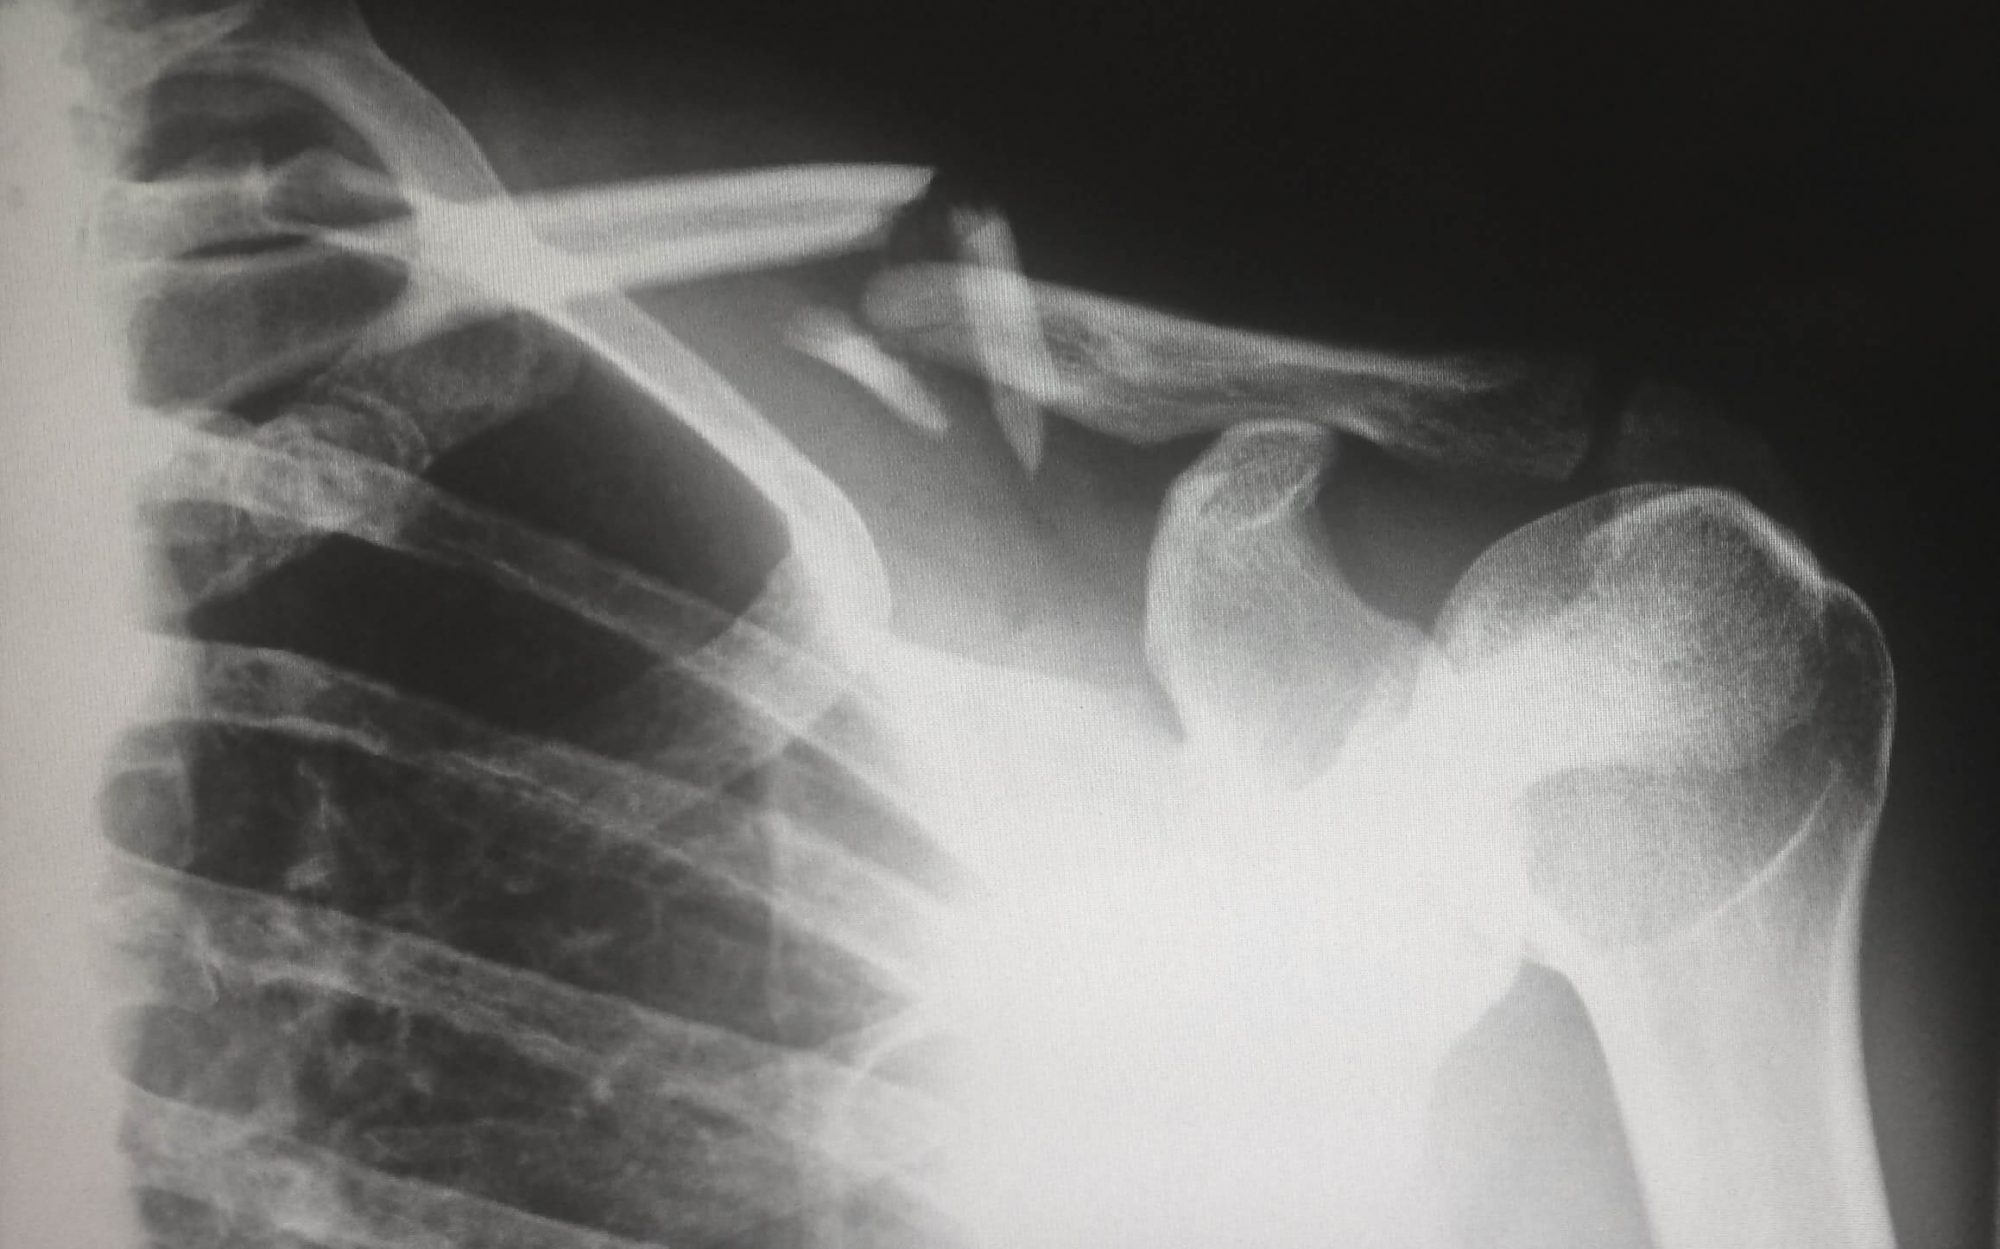

Pour aider à valider le logiciel, des radiologues musculo-squelettiques ont lu et annoté des fractures sur 2 626 radiographies d’épaules, de bras et de jambes de patients prises sur quatre sites de l’université américaine, dont au moins 140 examens par région du corps. Ces évaluations ont servi de « vérité de base » par rapport à laquelle Rayvolve devait être jugé.

Ensuite, trois groupes différents de médecins de UH ont été invités à identifier des fractures dans 186 cas choisis au hasard, avec et sans l’aide de l’outil d’IA. L’équipe de recherche a ensuite comparé les différences en termes de précision de détection des fractures, de sensibilité, de spécificité et de temps d’interprétation avec et sans l’outil d’IA.

Les résultats montrent que parmi tous les médecins de l’étude, la lecture des images à l’aide de la solution Rayvolve aurait augmenté la précision des diagnostics de 5,6 %. Aussi, le temps d’examen et d’interprétation aurait diminué de 27 %.

La sensibilité – la capacité de l’outil d’IA à aider à identifier de vraies fractures et à éviter les faux négatifs – aurait quant à lui été améliorée de 0,865 à 0,955 avec l’aide de l’outil d’IA. Et la spécificité – la capacité de l’outil d’IA à aider à identifier les os sains et à éviter les faux positifs – se serait également améliorée, passant de 0,826 sans l’outil d’IA à 0,831 avec celui-ci.